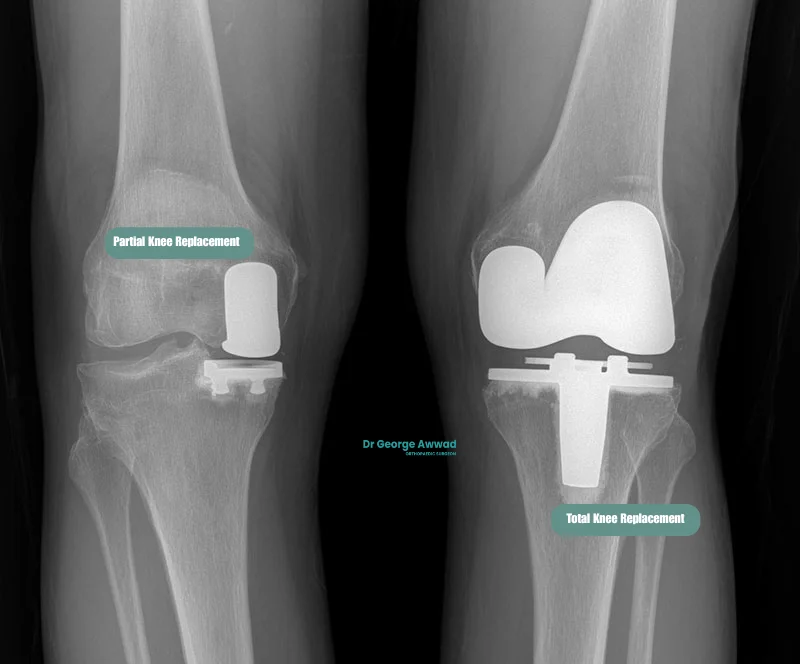

Partial knee replacement vs total knee replacement: which is right for you?

If you’re living with knee arthritis, one of the most important decisions in your treatment journey is whether to have a partial knee replacement (PKR) or a total knee replacement (TKR). Both procedures aim to relieve pain and improve function, but they differ in terms of surgical approach, recovery, and long-term considerations. The most appropriate option for you depends on the extent of arthritis in your knee, your overall health, lifestyle, and goals.

Key differences between partial and total knee replacement

Feature

Partial Knee Replacement (PKR)

Total Knee Replacement (TKR)

Extent of arthritis treated

One compartment only (typically medial, lateral, or patellofemoral)

Two or more compartments (always medial and lateral; patellofemoral joint may or may not be resurfaced)

Tissue preservation

Preserves more bone and ligaments

Replaces all joint surfaces and sometimes removes ligaments

Surgical invasiveness

Smaller incision, less bone removal

Larger incision, more comprehensive reconstruction

Recovery time

Generally faster recovery and shorter hospital stay

Longer initial recovery, more extensive physiotherapy

Knee function

Often retains more natural movement and feel

Reliable pain relief, but may feel more artificial

Suitability

Best for patients with isolated compartment arthritis

Suitable for widespread arthritis across the entire knee

Revision risk

May require conversion to TKR in future if arthritis spreads

Typically lasts longer with fewer additional surgeries required

1. Location and extent of arthritis

If your arthritis is confined to a single compartment of the knee and the rest of the joint is healthy; a partial knee replacement may be a suitable option. If multiple compartments are affected, a total knee replacement may be more effective.

2. Knee stability and alignment

Partial knee replacement relies on healthy surrounding ligaments, particularly the ACL. If there is instability or deformity in the knee, a total knee replacement may be more appropriate.